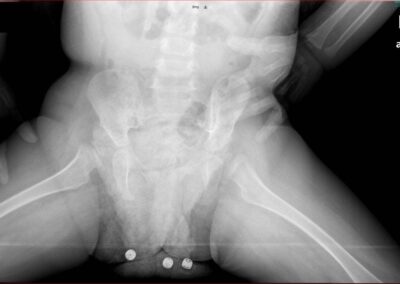

Congenital Pediatric Orthopedic DiseasesDec 30, 2021 | Case ExamplesBilateral GKD Case 1 Bilateral GKD Case 2 Bilateral GKD Case 3 Bilateral GKD Case 4 Congenital Clubfoot Fibuler Hemimeli Tibial Hemimeli PFFD